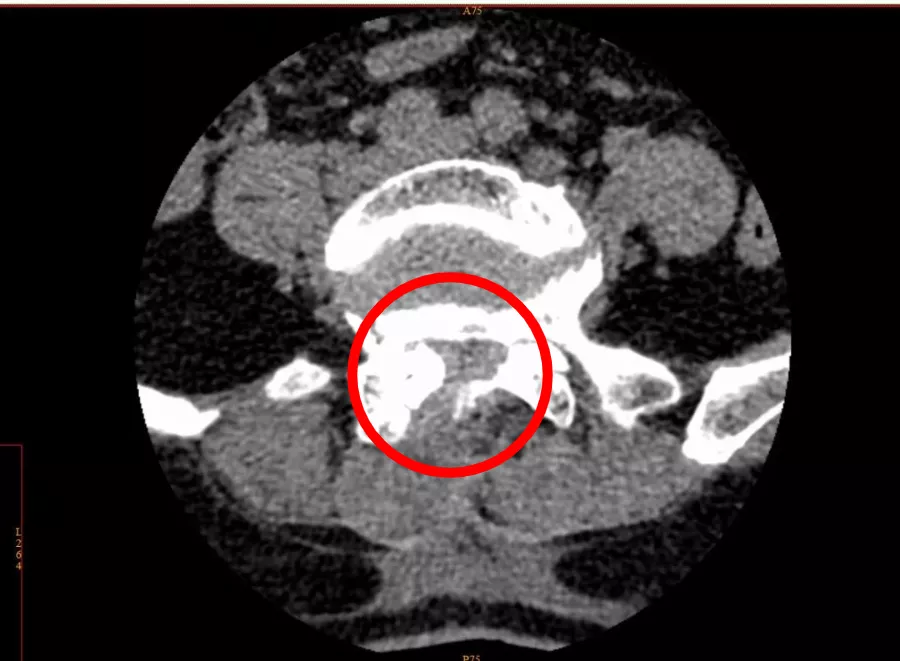

通过CT影像报告,疼痛科主任肖林发现了问题所在——腰椎管狭窄。

CT影像显示,李女士的腰椎管存在狭窄

肖林介绍,腰椎管是腰椎神经所在之处,腰椎神经支配着腰部及下肢关节,相当于城市中连接多个支干的主干道。腰椎管因髓核组织生长变狭窄后,便会压迫腰椎神经,使腰部产生强烈痛感,同时引起下肢疼痛。